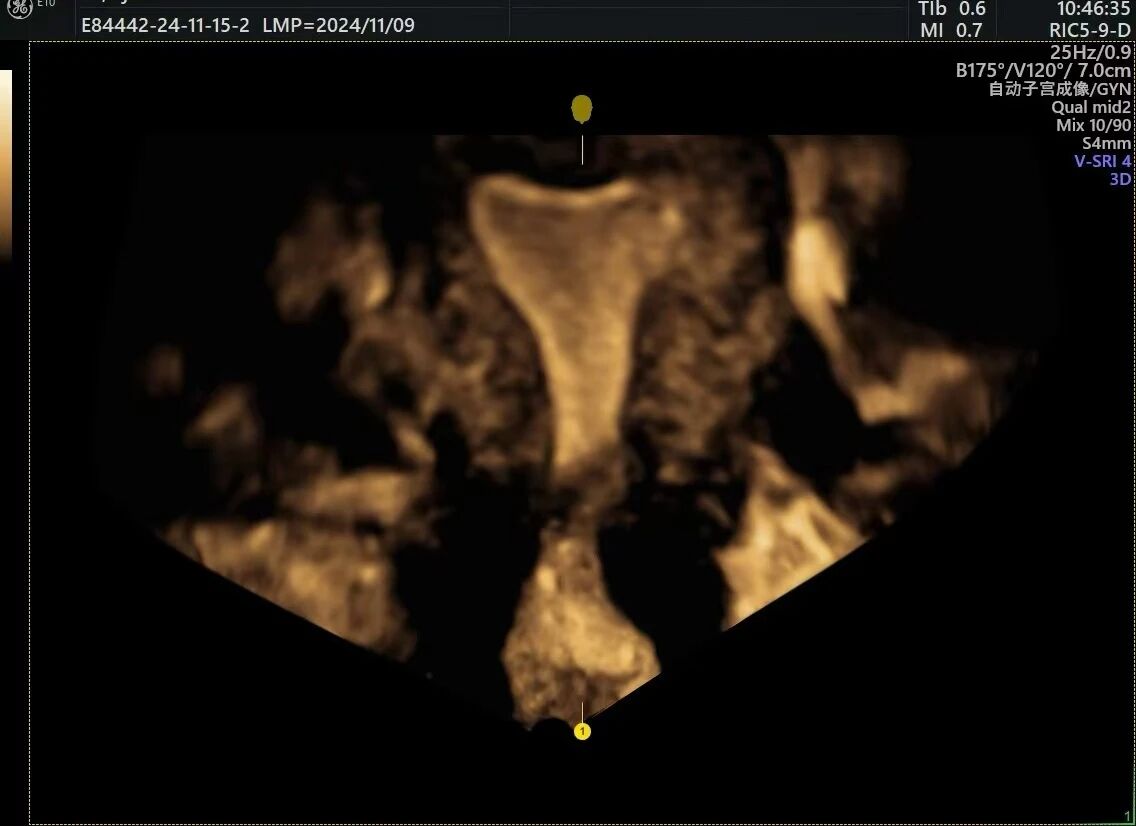

△子宫内膜三维成像

△输卵管三维成像